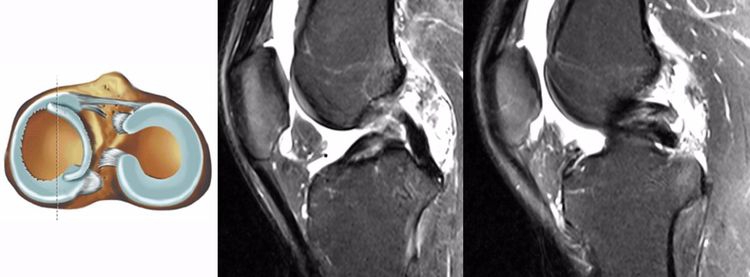

ACL最好的观察层面:最好的观察层面是斜矢状面,同时需要结合横断面和冠状面。

ACL最常见的撕裂部位:韧带实质部>韧带股骨髁附着部>韧带胫骨附着部。由于胫骨附着部多为撕脱骨折,DR及CT均能够清晰的显示,因此很多临床医生误认为胫骨附着部的发病率更高。

ACL损伤的直接征象:指ACL本身的形态和信号异常。一旦有了明确的直接征象就可以确定ACL损伤。

1.不连续:有韧带的低信号,但中断不连续。一般见于新鲜损伤。

2.方向异常(ACL 下垂征):有较完整的韧带低信号,但方向异常,呈下垂状。一般见于股骨附着部的陈旧损伤,损伤的ACL下垂并粘附在PCL上。

3.ACL 消失:髁间窝空虚,无韧带信号。见于较久的损伤,损伤的ACL撕裂较重呈马尾状,无滑膜包裹,逐渐被关节内的酶腐蚀而消失。

4.撕脱骨折:一般为ACL胫骨附着部的撕脱,韧带完整,信号多正常。

5.假瘤:韧带损伤后断端较整齐,残端组织增生并被滑膜包裹呈"瘤状",如果突出于前方为"独眼征",多见于韧带股骨附着部撕裂及部分撕裂。

6.扭曲和空虚:髁间窝内似隐隐约约有低信号,边缘明显,中央空虚;或者中央有低信号,但扭曲如麻花状。多为陈旧损伤,仅存ACL的滑膜,里面可有少量的韧带纤维,粘附在后方,随着膝关节的长时间屈伸逐渐呈扭曲状。